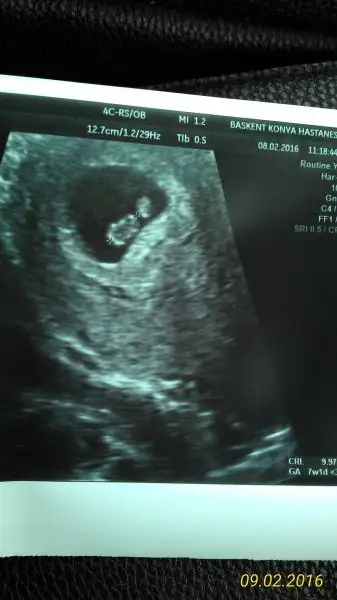

Kızlar doktordan geldik şimdi, kalp atışlarını duyduk çok şükür, zaten geç döllenmeydi 1 hafta geriden geliyoruz, 8 hafta dolmuş olmalıydı, tam 7 hafta dolmuş. Bebişimin kalbi çok güzel atıyor maşallah, fotoğrafımızı da çektirdik, 1 cm olmuşuz, doktorumuz artık mercimeklikten yer fıstığı olmuşuz dedi. Darısı bekleyen tüm arkadaşlara, Rabbim mucizene şükürler olsun, bu da fotoğrafımız:)